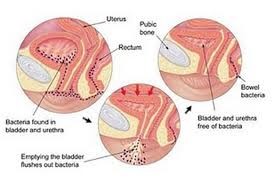

Οι ουρολοιμώξεις αφορούν λοιμώξεις του ουροποιητικού συστήματος των γυναικών, συγκεκριμένα στα νεφρά και στην ουροδόχο κύστη, και στο ουροποιητικό και αναπαραγωγικό σύστημα των ανδρών, συγκεκριμένα στα νεφρά στην κύστη στον προστάτη και στην επιδυδιμίδα-όρχεις. Οι γυναίκες έχουν μεγαλύτερη πιθανότητα να εμφανίσουν στη ζωή τους ουρολοίμωξη λόγω της ειδικής ανατομίας του ουροποιητικού τους και συγκεκριμένα του μήκους της ουρήθρας (περίπου 3 εκατοστά), στο γεγονός ότι η ουρήθρα εκβάλλει στον κόλπο και είναι πολύ κοντά στον πρωκτό, ένα σημείο που συνήθως βρήθει μη παθογόνων μικροβίων τα οποία όμως πολύ εύκολα μπορούν να βρεθούν εντός της κύστεως καθώς και στην κακή συνήθεια των γυναικών να αναβάλλουν επί μακρόν τις ουρήσεις τους όταν βρίσκονται εκτός της οικίας τους. Άλλοι λόγοι είναι η χρήση κάποιων μέσων αντισύλληψης (σπιράλ, διάφραγμα), η δημιουργία μικροτραυματισμών κατά την σεξουαλική επαφή καθώς και η εμμηνόπαυση λόγω της δραματικής μείωσης των οιστρογόνων αλλάζει η χλωρίδα και το ph με αποτέλεσμα τον πιο εύκολο αποικισμό του από παθογόνα μικρόβια.